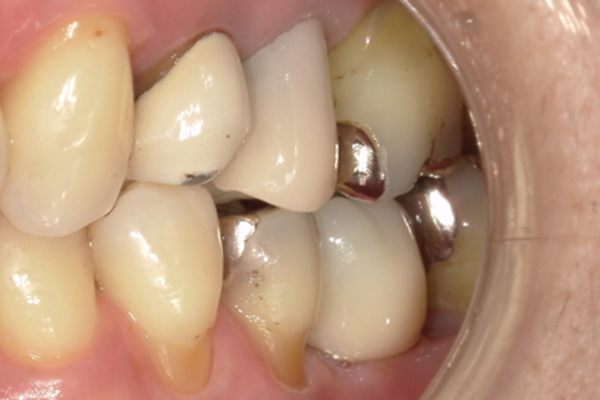

| 主訴 | 右下の奥歯が痛い |

|---|---|

| 治療内容 | 右下奥歯が割れていたため抜歯、その後インプラント治療を行った。(左の写真は抜歯後の写真) |

| 治療期間 | 4ヶ月 |

| 治療費 | 41万5千円 |

| 治療 リスク | 抜歯後インプラントの処置まで3ヶ月程度治癒期間(骨ができるまでの期間)が必要なことがあります。 |